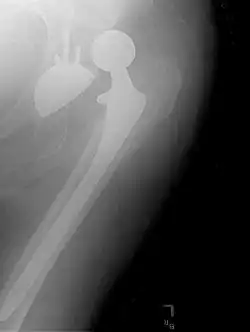

.jpg)

Hemiarthroplasty is a surgical procedure that replaces one half of the joint with an artificial surface and leaves the other part unchanged. This class of procedure is most commonly performed on the hip after an intracapsular fracture of the femur neck (hip fracture). The procedure is performed by removing the head of the femur and replacing it with a metal or composite prosthesis. The most commonly used prosthesis designs are the Austin Moore and Thompson prostheses. A composite of metal and high-density polyethylene that forms two interphases (bipolar prosthesis) can be used. The monopolar prosthesis has not been shown to offer any advantage over bipolar designs. The procedure is recommended only for elderly/frail patients, due to their lower life expectancy and activity level. This is because over time the prosthesis tends to loosen or to erode the acetabulum.[110] Independently mobile older adults with hip fractures may benefit from a total hip replacement instead of hemiarthroplasty.[111]

Hip prosthesis for hemiarthroplasty. This example is bipolar, meaning that the head has two separate articulations.

X-ray of the hips, with a right-sided hemiarthroplasty